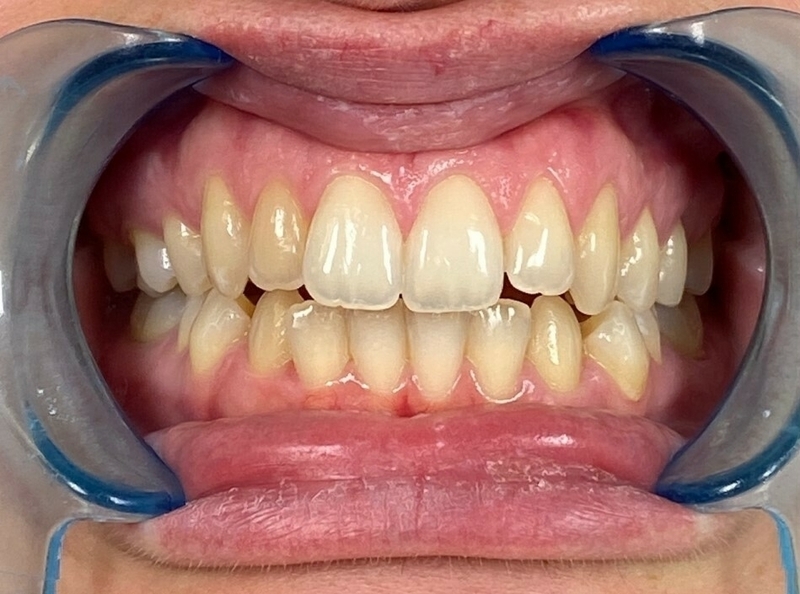

Cas clinique

Cas 1 - Orthodontie par aligneurs invisibles

Après